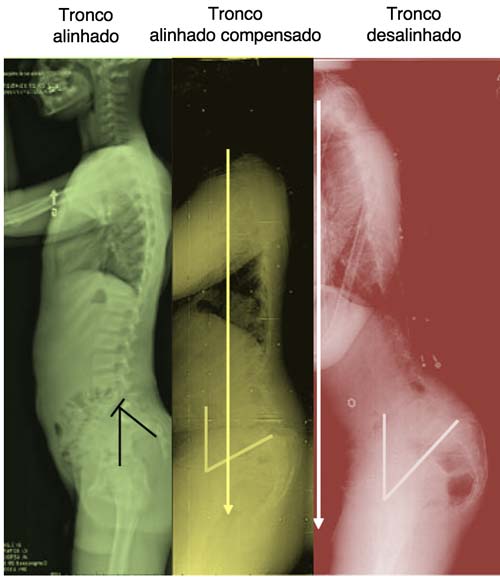

A lordose é a curvatura natural da coluna lombar, aquela que faz a parte de baixo das suas costas se curvar para dentro. Pense nela como um “S” suave. Essa curva é essencial para a gente se movimentar bem, absorver impactos e manter o equilíbrio. Sem ela, andar e sentar seria bem mais difícil!

Quando essa curvatura aumenta demais, a gente chama de lordose acentuada. Isso pode vir de má postura, fraqueza muscular ou até de ganho de peso. O importante é saber que dá para cuidar dessa região. Manter os músculos fortes e a postura correta são passos chave para um alívio.